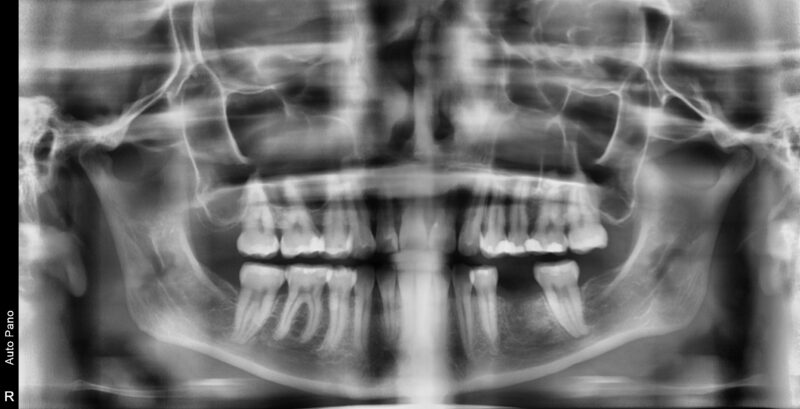

Hi I extracted tooth # 19 about 4 months ago and grafted it with 50/50 cortical cancellous bone and resorbable membrane.

I saw the pt today and felt like the bone could be more dense in the extraction site. Looking at the photos you can see that the ridge was 9.7mm and now it’s 7.8mm after 4 months.

I was going to drop a 4.5x 8.5 in the site, but ideally I wish I could put a 5mm into the area.